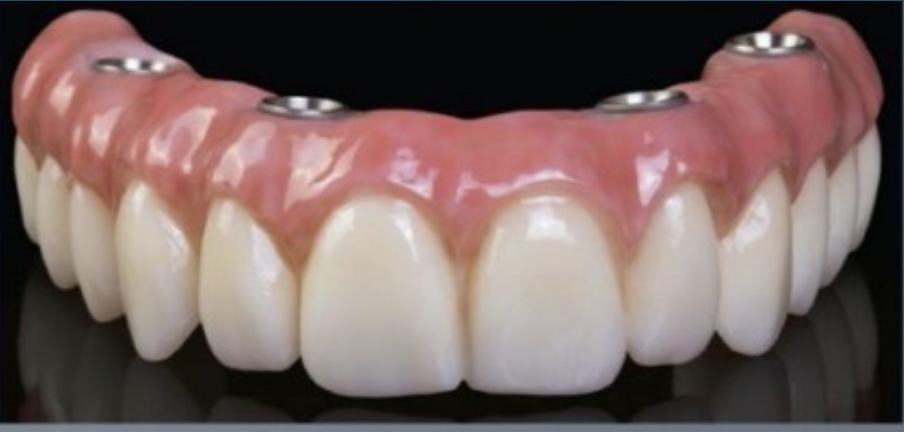

Patient Factors that May Contraindicate Fixed Implant-supported Prosthetics

At the initial patient examination, several factors in addition to restoration shape should be considered when planning implant-supported restorations. History of periodontal disease, irregular maintenance visits, clinical appearance of the remaining teeth and soft tissue conditions may indicate increased risk of peri-implantitis. Patient dexterity, adaptability, willingness, and capability to carry out intended home care should be considered. Patient's mental conditions including dementia may influence the design of this as well as unrealistic patient expectations. A "High water original Branemark design" or no treatment may be indicated. Especially when implant location makes access, a fixed-removable design may be necessary to reduce risk of peri-implantitis may be indicated (Figures 42 through Figure 45). Considering that oral biofilm accumulation, even at two weeks post prosthetic insertion is documented, periodic removal of screw retained restorations is less effective than daily access to disrupt bacterial plaque accumulation.

(42.) Fixed-removable prosthesis.

Figure 42

(43.) Fixed-removable prosthesis.

Figure 43

(44.) Fixed-removable prosthesis.

Figure 44

(45.) Fixed-removable prosthesis.

Figure 45